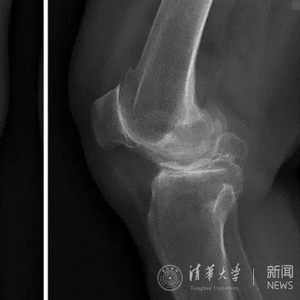

69岁的顾女士,已经有10年的右膝关节骨性关节炎病史,尝试了所有保守治疗后,膝关节疼痛未得到有效缓解,严重影响了生活。经介绍,患者找到北京清华长庚医院骨科关节中心主任蔡谞教授,希望进行膝关节置换手术。

患者术前膝关节正侧位平片。